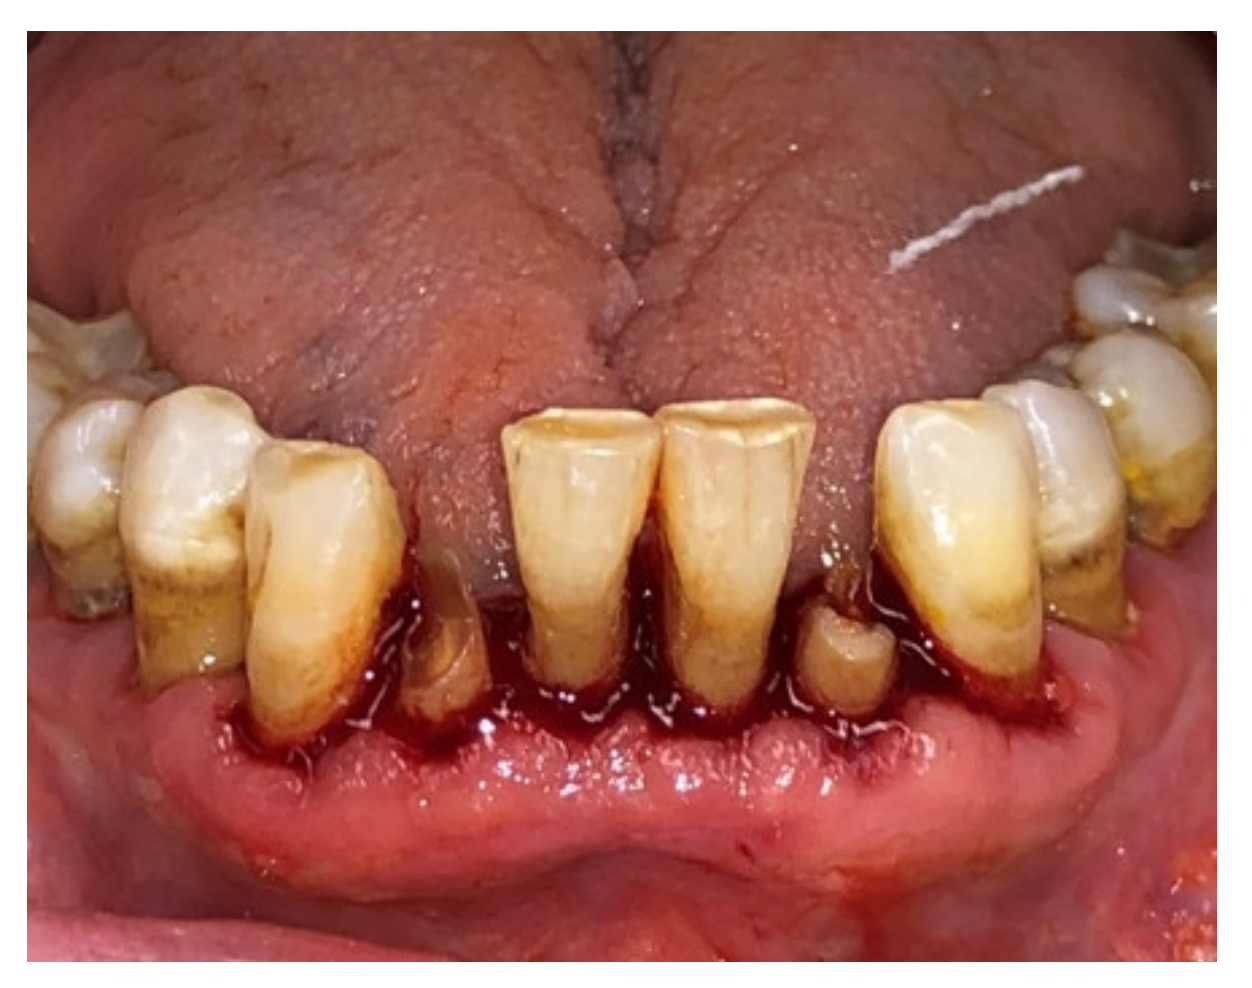

| Tissue colour: | 50% of gingiva red |

| Granulation tissue: | Present | |

| Incision margin: | Not epithelialized, with loss of epithelium beyond incision margin | |

| Suppuration: | Present | |

| Incision margin: | Not epithelialized, with connective tissue exposed | |

| Suppuration: | None | |

| Granulation tissue: | None | |

| Incision margin: | No connective tissue exposed | |

| Tissue colour: | 25% of gingiva red |

| Tissue colour: | All tissues pink |

| Suppuration: | None |